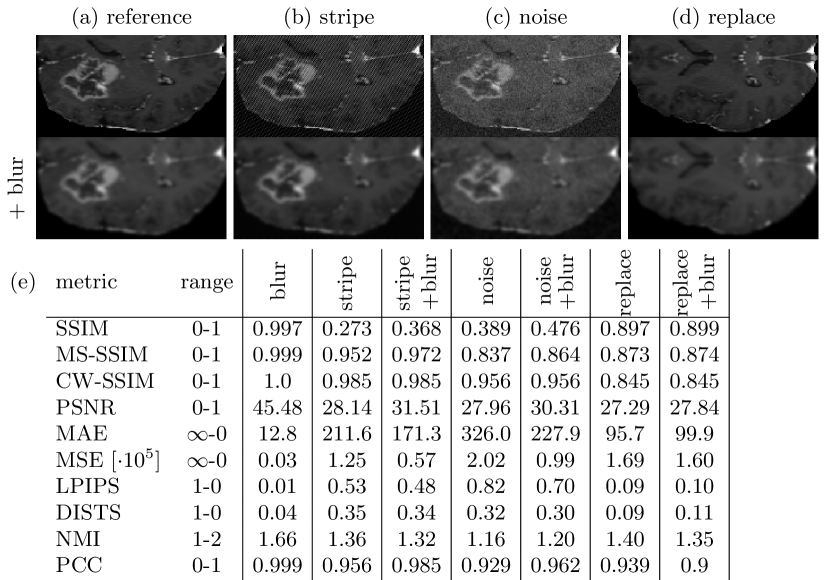

3.4 Pitfall 4: Error Metrics Prefer Blurred Images

When using loss functions based on error metrics, such as MSE, it has been reported and observed, that optimized models generate blurry images [18]. We assessed metric scores for three kinds of distortions and also for the undistorted images with additional blurring. We observe, that metric scores increase for the additionally blurred versions. The distortions are also perceived as weakened by the blurring. However, the overall quality and degree of blurriness is not satisfactory and we assume further blurring will not arbitrarily improve similarity. The metric score results and example images are shown in Fig. 4.